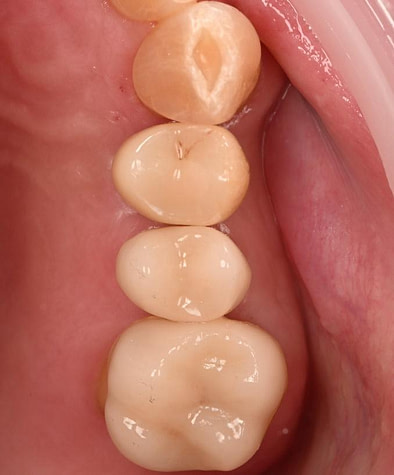

Digital impressions were captured using the TRIOS 4 intraoral scanner, and the implant-supported crown was designed using 3Shape Design Studio.

The crown was milled from a high-strength, multilayered zirconia and hand-finished to achieve a lifelike appearance.

At the final appointment, the crown was securely attached to the implant, resulting in a beautiful, natural-looking restoration.

The successful completion of the implant treatment was evaluated based on aesthetics, function, and patient satisfaction.

The implant-supported crown seamlessly integrated with the patient's natural dentition, and the patient reported excellent comfort and function.

A radiographic assessment confirmed the proper integration and positioning of the implant.